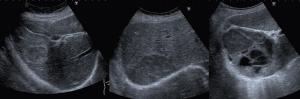

肝硬度測定

肝硬変の方は肝蔵の硬さをshear wave elastographyで画像化及び定量化して評価しています。慢性的な肝疾患では線維化が進展すると組織の硬度が増し、発癌リスクが増加します。そのため肝蔵の線維化を調べるのは極めて重要です。

Attenuation Imaging-R

生体内部に放射された超音波パルスは生体組織を通過するときに次第に拡散し熱となって生体組織に吸収されたり散乱によって減衰したりします。組織内の超音波周波数依存性減衰の程度を計測し減衰係数を表示する技術です。これにより脂肪肝の診断が数値で評価できるようになりました。